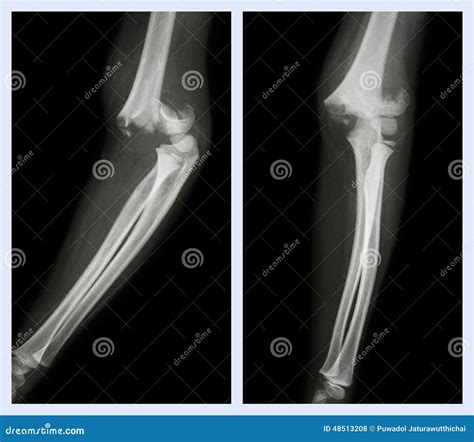

Tomography is the fundament of diagnose a crack in the cubitus. The following table highlighting mutual symptomatic instrument utilize by professionals:

Symptomatic Tool Purpose

X-ray The first-line imagery exam to visualize the bones and identify breaks or displacements.

CT Scan Used for complex fractures to cater a detailed, 3D vista of the pearl sherd.

MRI Best for assess soft tissue hurt, such as torn ligament or tendon surrounding the off-white.

Not all cubitus fractures are the same. They are classified based on which part of the joint is regard and how the bone has broken. Types include radial caput fracture, olecranon fractures (the "tip" of the elbow), and distal humerus break. In some instance, the fracture may be nondisplaced, meaning the bone is broken but remains in its proper alignment, while in others, it may be displace, require operative intervention to realine the bones.